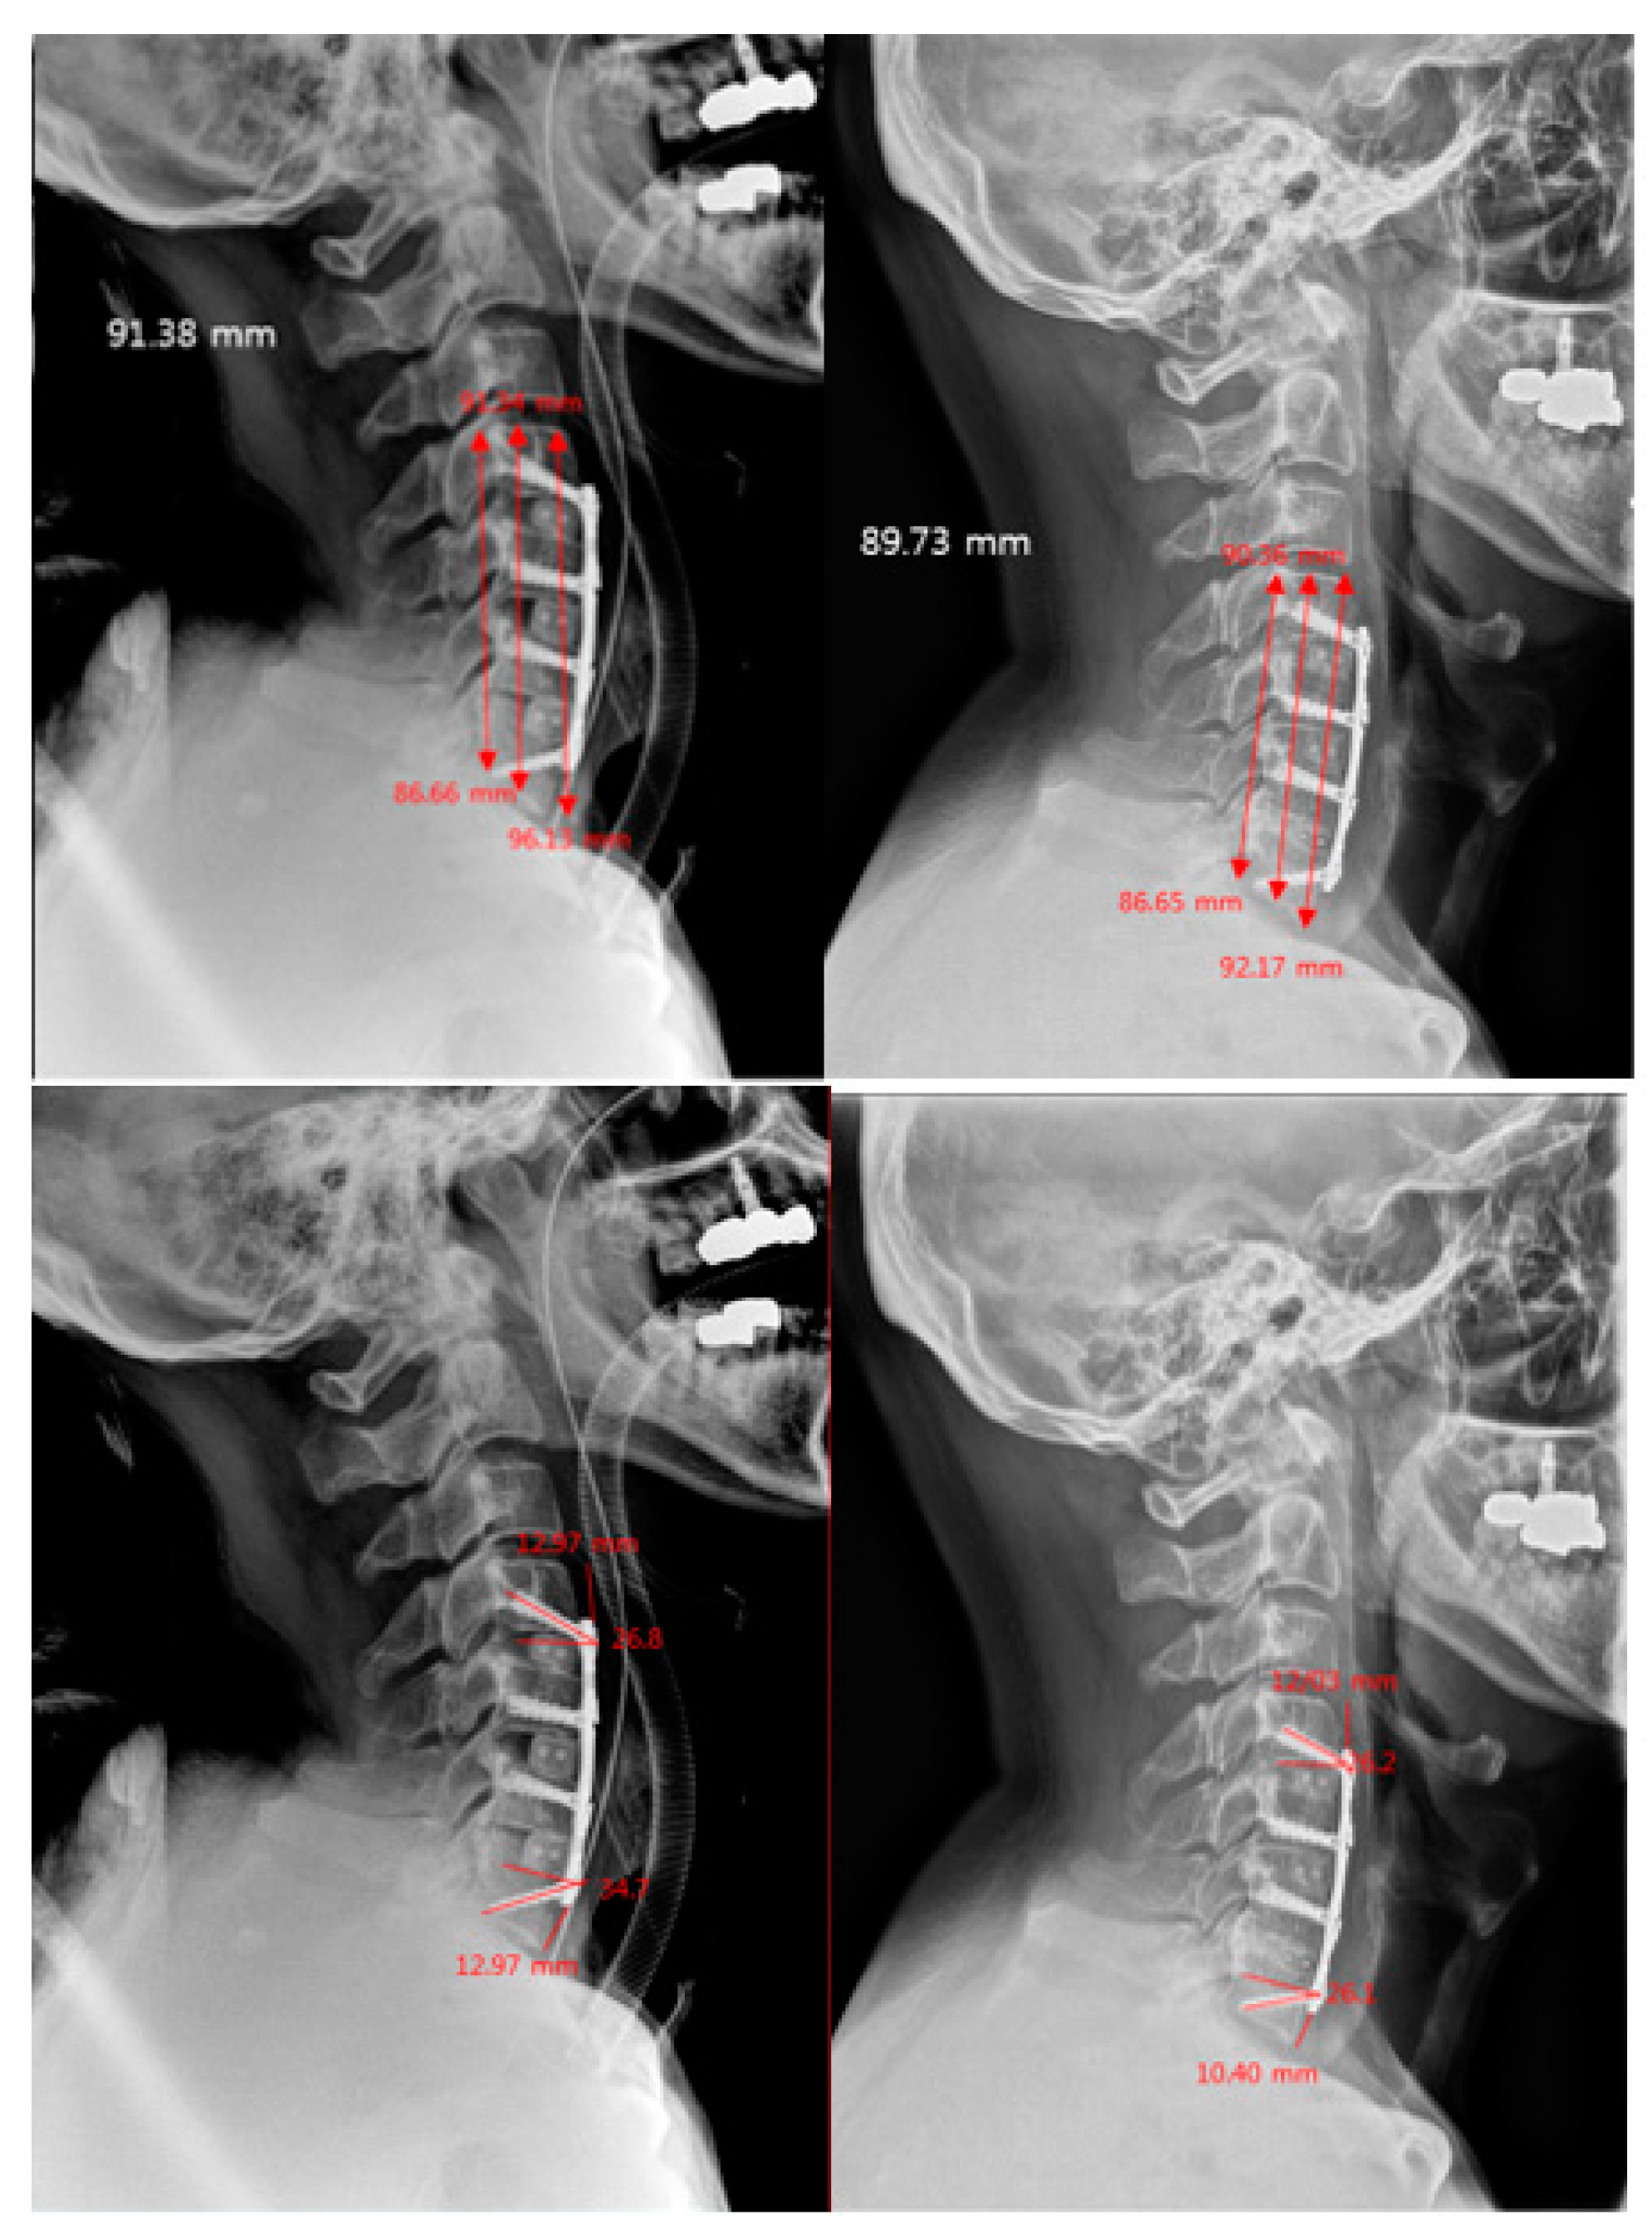

- Plate-to-Disc Distance: distance from the most proximal part and most distal part of the plate to the superior and inferior adjacent disc spaces, respectively [13].

- Screw Angles: angle between a line perpendicular to the plate and the direction of the screw [6].

- Subsidence: the vertical length from the superior endplate of the most superior vertebra to the inferior endplate of the most inferior vertebra [14].

| Plate-to-Disc Distance (mm) Superior | 10.7 ± 2.3 | 4.7 ± 1.8 | 8.3 ± 3.6 | <0.001 |

| Plate-to-Disc Distance (mm) Inferior | 9.0 ± 2.0 | 4.0 ± 1.0 | 7.0 ± 3.0 | <0.001 |

| Screw Angle Superior | 22.8 ± 5.3 | 12.3 ± 2.5 | 18.5 ± 6.8 | <0.001 |

| Screw Angle Inferior | 23.3 ± 4.7 | 13.2 ± 3.2 | 19.2 ± 6.5 | <0.001 |

| Screw Angle Superior | 21.4 ± 5.0 | 11.0 ± 2.5 | 17.2 ± 6.6 | <0.001 |

| Screw Angle Inferior | 22.0 ± 4.6 | 11.8 ± 3.6 | 17.9 ± 6.5 | <0.001 |

| Screw Angle Superior | 20.9 ± 5.0 | 10.7 ± 2.6 | 16.7 ± 6.6 | <0.001 |

| Screw Angle Inferior | 20.9 ± 5.0 | 11.2 ± 3.5 | 17.0 ± 6.5 | <0.001 |

| Subsidence Rate | 1.9 ± 1.8 | 3.2 ± 2.7 | 2.5 ± 2.3 | 0.017 |

| Subsidence >3 mm (n, %) | 4 (8.5) | 8 (25.0) | 12 (15.2) | 0.045 |